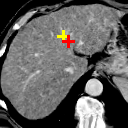

Refer to caption

(a)

(b)

(c) 12.49

(d) 0.9420

(e) 12.44

(f) 0.8593

(g) 13.28

(h) 0.8612

(i) 19.20

(j) 0.7311

Figure 6: Example comparison among VTN ADDD + inv (c/d), Elastix (e/f), ANTs (g/h) and VoxelMorph-2 (i/j). (a) sections of the fixed image (a CT liver scan); (b) sections of the moving image (another CT liver scan); (c/e/g/i) sections of the warped images and landmark distances; (d/f/h/j) sections of the warped segmentations (white for the fixed and semi-transparent red for the warped) and segmentation IoUs. Crosses indicate the projection of landmarks (L2, L3 and L4 from top to bottom), yellow (lighter) for one in the fixed image, red (darker) for the corresponding one in the moving/warped images. Best viewed in color.